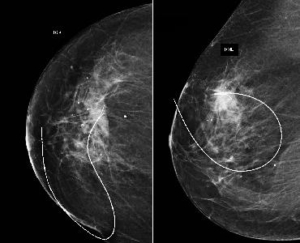

Non-palpable breast masses require a distinct approach within breast health management. When a patient or doctor detects a lump during physical examination, diagnosis and treatment are relatively straightforward. However, in cases where the patient has no symptoms and no findings are evident upon examination, but imaging techniques like mammography or ultrasound reveal a suspicious area, a different strategy is needed.

Because these masses cannot be felt and their exact location is harder to determine, diagnostic and treatment procedures must be more precise. In the past, when medical techniques were less advanced, suspicious areas in the breast were removed based on estimates, which sometimes led to incomplete excision or missed cancerous tissue, as revealed in subsequent imaging.

Today, advanced methods such as image-guided localization enable accurate marking of the suspicious region, ensuring precise identification and removal of the affected tissue. This progress significantly improves both diagnostic accuracy and treatment outcomes for non-palpable breast lesions.

Marking Non-Palpable Breast Masses

Non-palpable breast lesions hold significant importance, as they often represent the earliest stages of cancer. Identifying and closely evaluating such lesions enables early detection of cancer or precancerous changes, offering the opportunity to treat the condition at its earliest stage.

This approach significantly increases the chances of the patient maintaining a normal, healthy life.